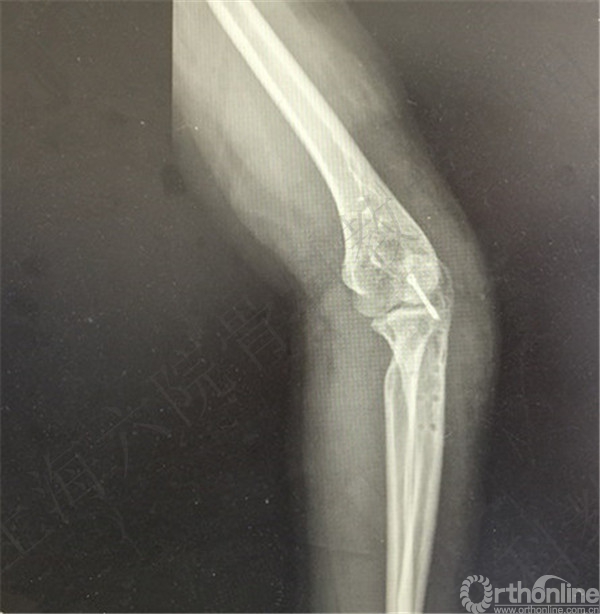

患者左尺骨鹰嘴骨折,取出内固定。

术后X线摄片示:左尺骨鹰嘴内固定取出,空心钉留置。

医方在术前未充分告知患者存在内固定取出困难、断钉、留置内固定、术中骨折和术后在骨折等风险。医方存在告知缺陷等过失。